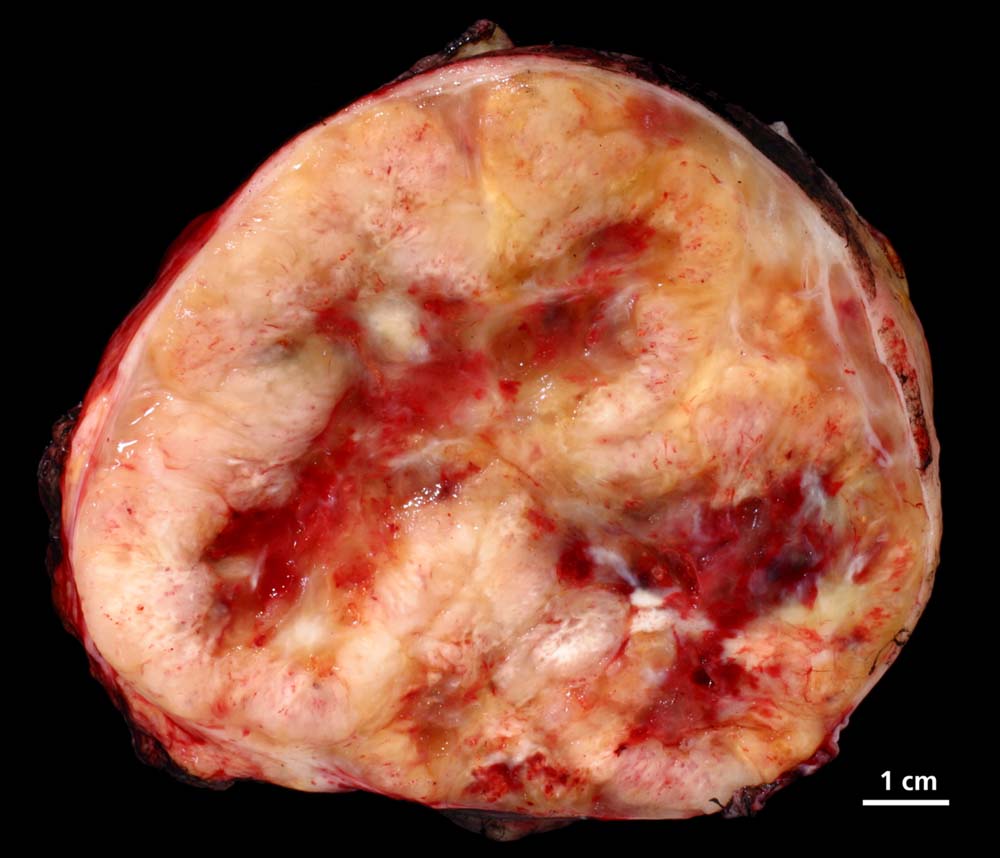

Makroskopisch imponieren Schwannome als scharf begrenzte, derbe, teils zystische Tumoren mit einer Grösse von bis zu 10 cm. Einblutungen sind möglich. Ausser bei Lokalisation im Knochen, in viszeralen Organen oder der Haut sind Neurinome meist abgekapselt. Gelegentlich erkennt man im Randbereich des Neurinoms Anteile des zur Seite verdrängten peripheren Nerven. In peripheren Tumoren lässt sich aber in weniger als der Hälfte der Fälle ein assoziierter Nerv identifizieren. Im Gegensatz zum Neurofibrom, welches den betroffenen Nerven infiltriert, lassen sich beim Schwannom intratumoral keine axonalen Strukturen nachweisen (Holmes Luxol Färbung).